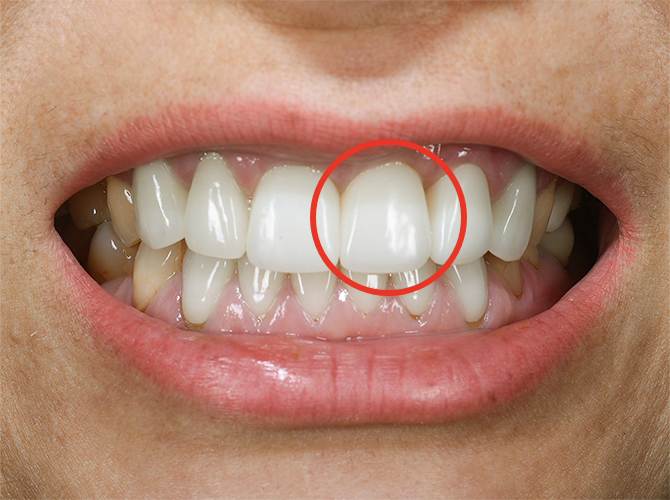

審美性と機能性を兼ね備えた仕上がり

前歯は特に審美にこだわり、天然歯と区別がつかないほどの自然な仕上がりを目指しています。

顎関節の治療を行う当院では、インプラントをする部位だけでなく、顎を含めた口腔内全体の治療方針を立てられます。インプラント部分の咬み合わせだけでなく、顎関節との調和を図りながらの治療をすすめ、審美面も機能性でも身体に調和した治療を行います。

自然な歯を求める方

大学時代にモデル事務所から前歯を整えるように言われ、神経を抜く手術を受けました。あまりの痛みに治療を続けられず放置してしまい、抜歯に。

前歯数本が仮歯の状態なのをずっと気にしていたところ、歯科衛生士の母のかかりつけ医院である川越歯科医院がインプラントをしていると聞き、来院しました。

| 治療内容 | 長い間仮歯の状態。インプラントを埋め込み、天然歯のような自然な仕上がりを目指す。 前歯2本を抜歯し、同時に3本のインプラント埋入とGBR(歯槽骨を再生する治療)を行う。長い治療期間でも生活の質を保つために、口腔内の状況に合わせた仮歯を装着。 |

笑った時に自然な口元になりたいという思いでお願いしました。母が「何とかなりませんか?」と相談した際も「治療期間が長くなるけれど、時間をかけてでも綺麗な仕上がりになるようなんとかします」と私に合った方法を考えてくれました。

先生から一言

術後、泣いて喜んでくださったのを覚えています。笑った時のスマイルラインも自然で、人工歯には思えません。天然歯かインプラントか、歯医者さんが見ても分からないと思います。